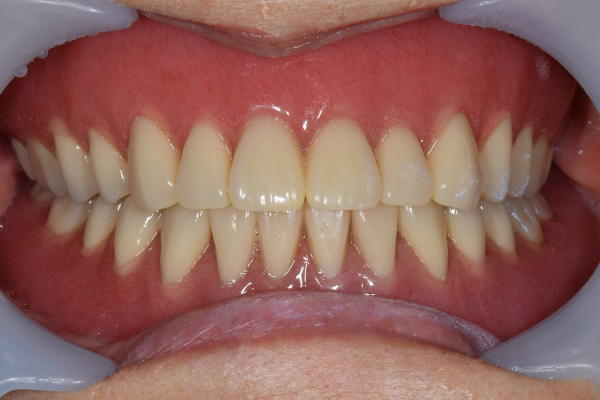

金属を使用して、薄く違和感が少ない入れ歯が完成しました。 また、見た目にも気を使い、バネが見えにくい様な構造にしました。

入れ歯をお口の中にいれた状態です。前歯もMTMといって、歯を少し引っ張り出す処置を行なったことで、しっかり残せて、またかぶせ物をしました。

義歯は下顎で、しっかり噛めること、違和感の少ないものという希望があったため、なるべく入れ歯を薄く作成するために金属をしようした義歯とした。

また、見た目もあまり義歯が目立たない様に、バネの部分を見えにくいように作成した。

お口の中に入れた状態です。 見た目も最初とほとんど変わることなく作成できました。 維持や吸着に関しても問題ないようでした。